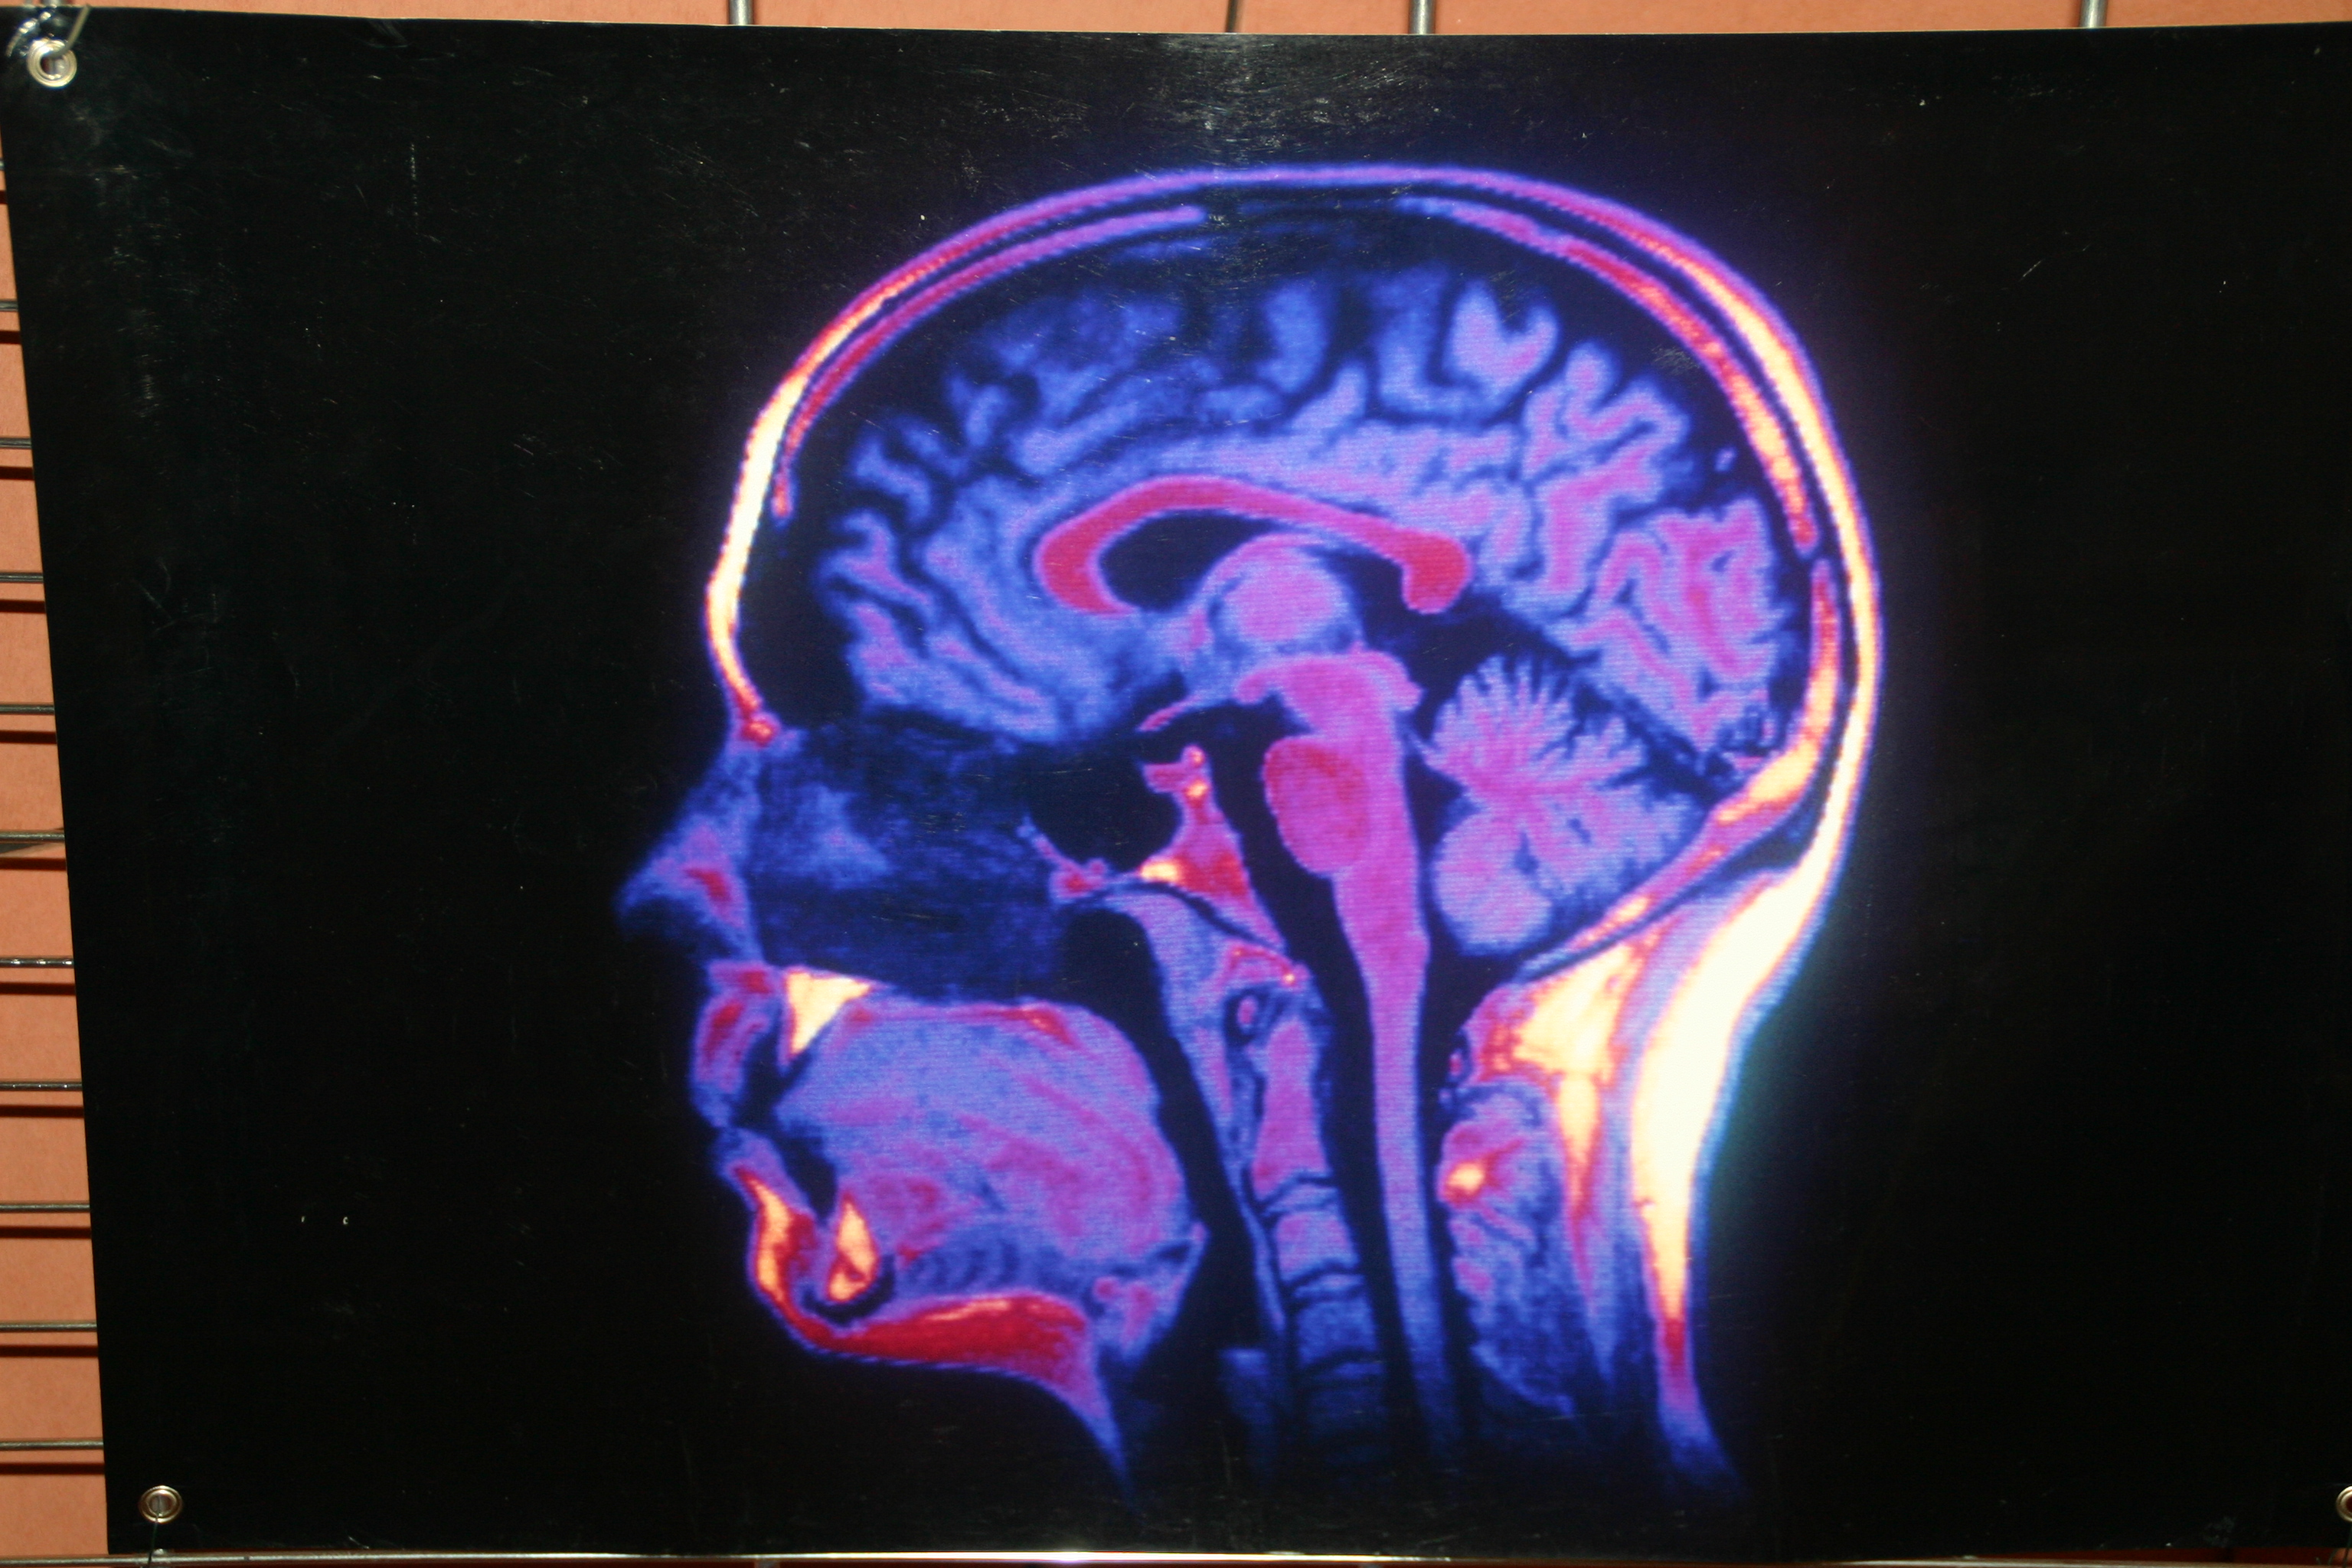

Coordonnée par l’association Cerveau Point Comm, sous l’égide de la Société française des neurosciences, relayée dans les Hautes-Alpes par Gap sciences animation 05, cette manifestation propose au grand public de venir à la découverte des dernières avancées de la recherche sur le cerveau en affichant de superbes images d’I.R.M. en couleurs avec les explications nécessaires. Au micro de Gilles Rey, Eric Gerbault, coordinateur de Gap Sciences Animations 05 présente cet évènement et les actus à venir notamment une conférence vendredi 10 avril sur le thème de cerveau et surdité, puis Fabienne Depalma, responsable de la bibliothèque universitaire de Gap rappelle les mérites de cet établissement méconnu du grand public.